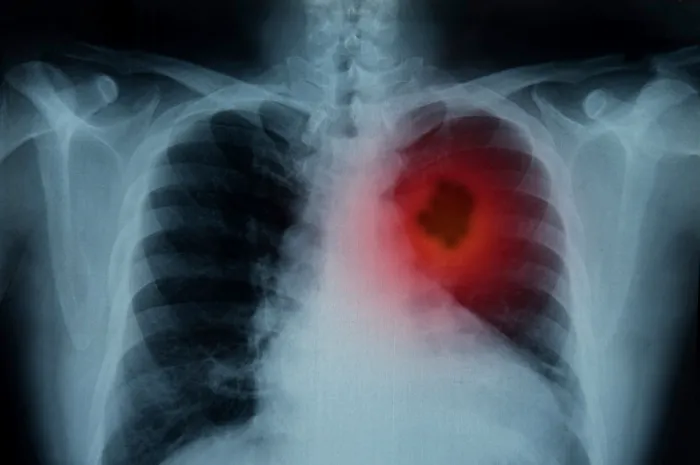

“Oamenii care resimt probleme respiratorii se duc mai întâi la radiologie. Această investigaţie este foarte utilă, dar presupune iradiere şi nu vedem decât modificări anatomice când sunt destul de importante. În schimb, spirometria este o investigaţie total neinvazivă şi nu presupune expunere la radiaţii, iar evaluarea funcţiei pulmonare se poate face timpuriu”

Magdalena Ciobanu, medic primar pneumolog